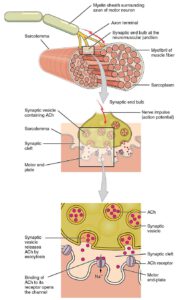

Anatomy and Physiology

Cheatsheets

17

Mnemonics

6

Images

60